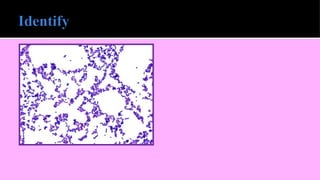

 Gram-positive bacteria resist decolorization and retain the

color of primary stain i.e. violet.

 Gram-negative bacteria are decolorized and, therefore, take

counterstain and appear pink

Gram positive cocci Gram negative cocci Gram negative

bacilli

Gram positive bacilli